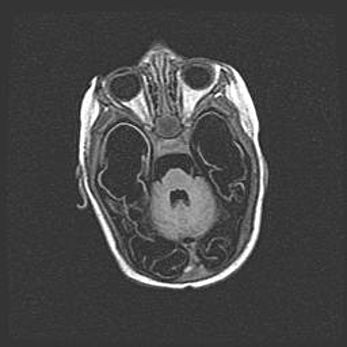

Неполная лизэнцефалия (пахигирия). Открытая гидроцефалия.

Возраст: 17 дней

Вес: 3110 г

Пол: мужской

Окружность головы: 33,5 см

Срок гестации: 35-36 недель

Лизэнцефалия—недоразвитие корковой пластинки и мозговых извилин в результате нарушения миграции нейронов коры. Поверхность мозговых полушарий гладкая. Микроскопически выявляется отсутствие нормальных слоев коры и скопление групп нейронов в подкорковом белом веществе.

Пахигирия—уменьшение числа вторичных извилин. В пораженном полушарии нервные клетки образуют толстый недифференцированный слой с неправильно расположенными нервными волокнами и группами гетеротопных клеток. Нервные клетки незрелые. Белое вещество истончено. При этом нередко аномально развит корково-спинномозговой путь.